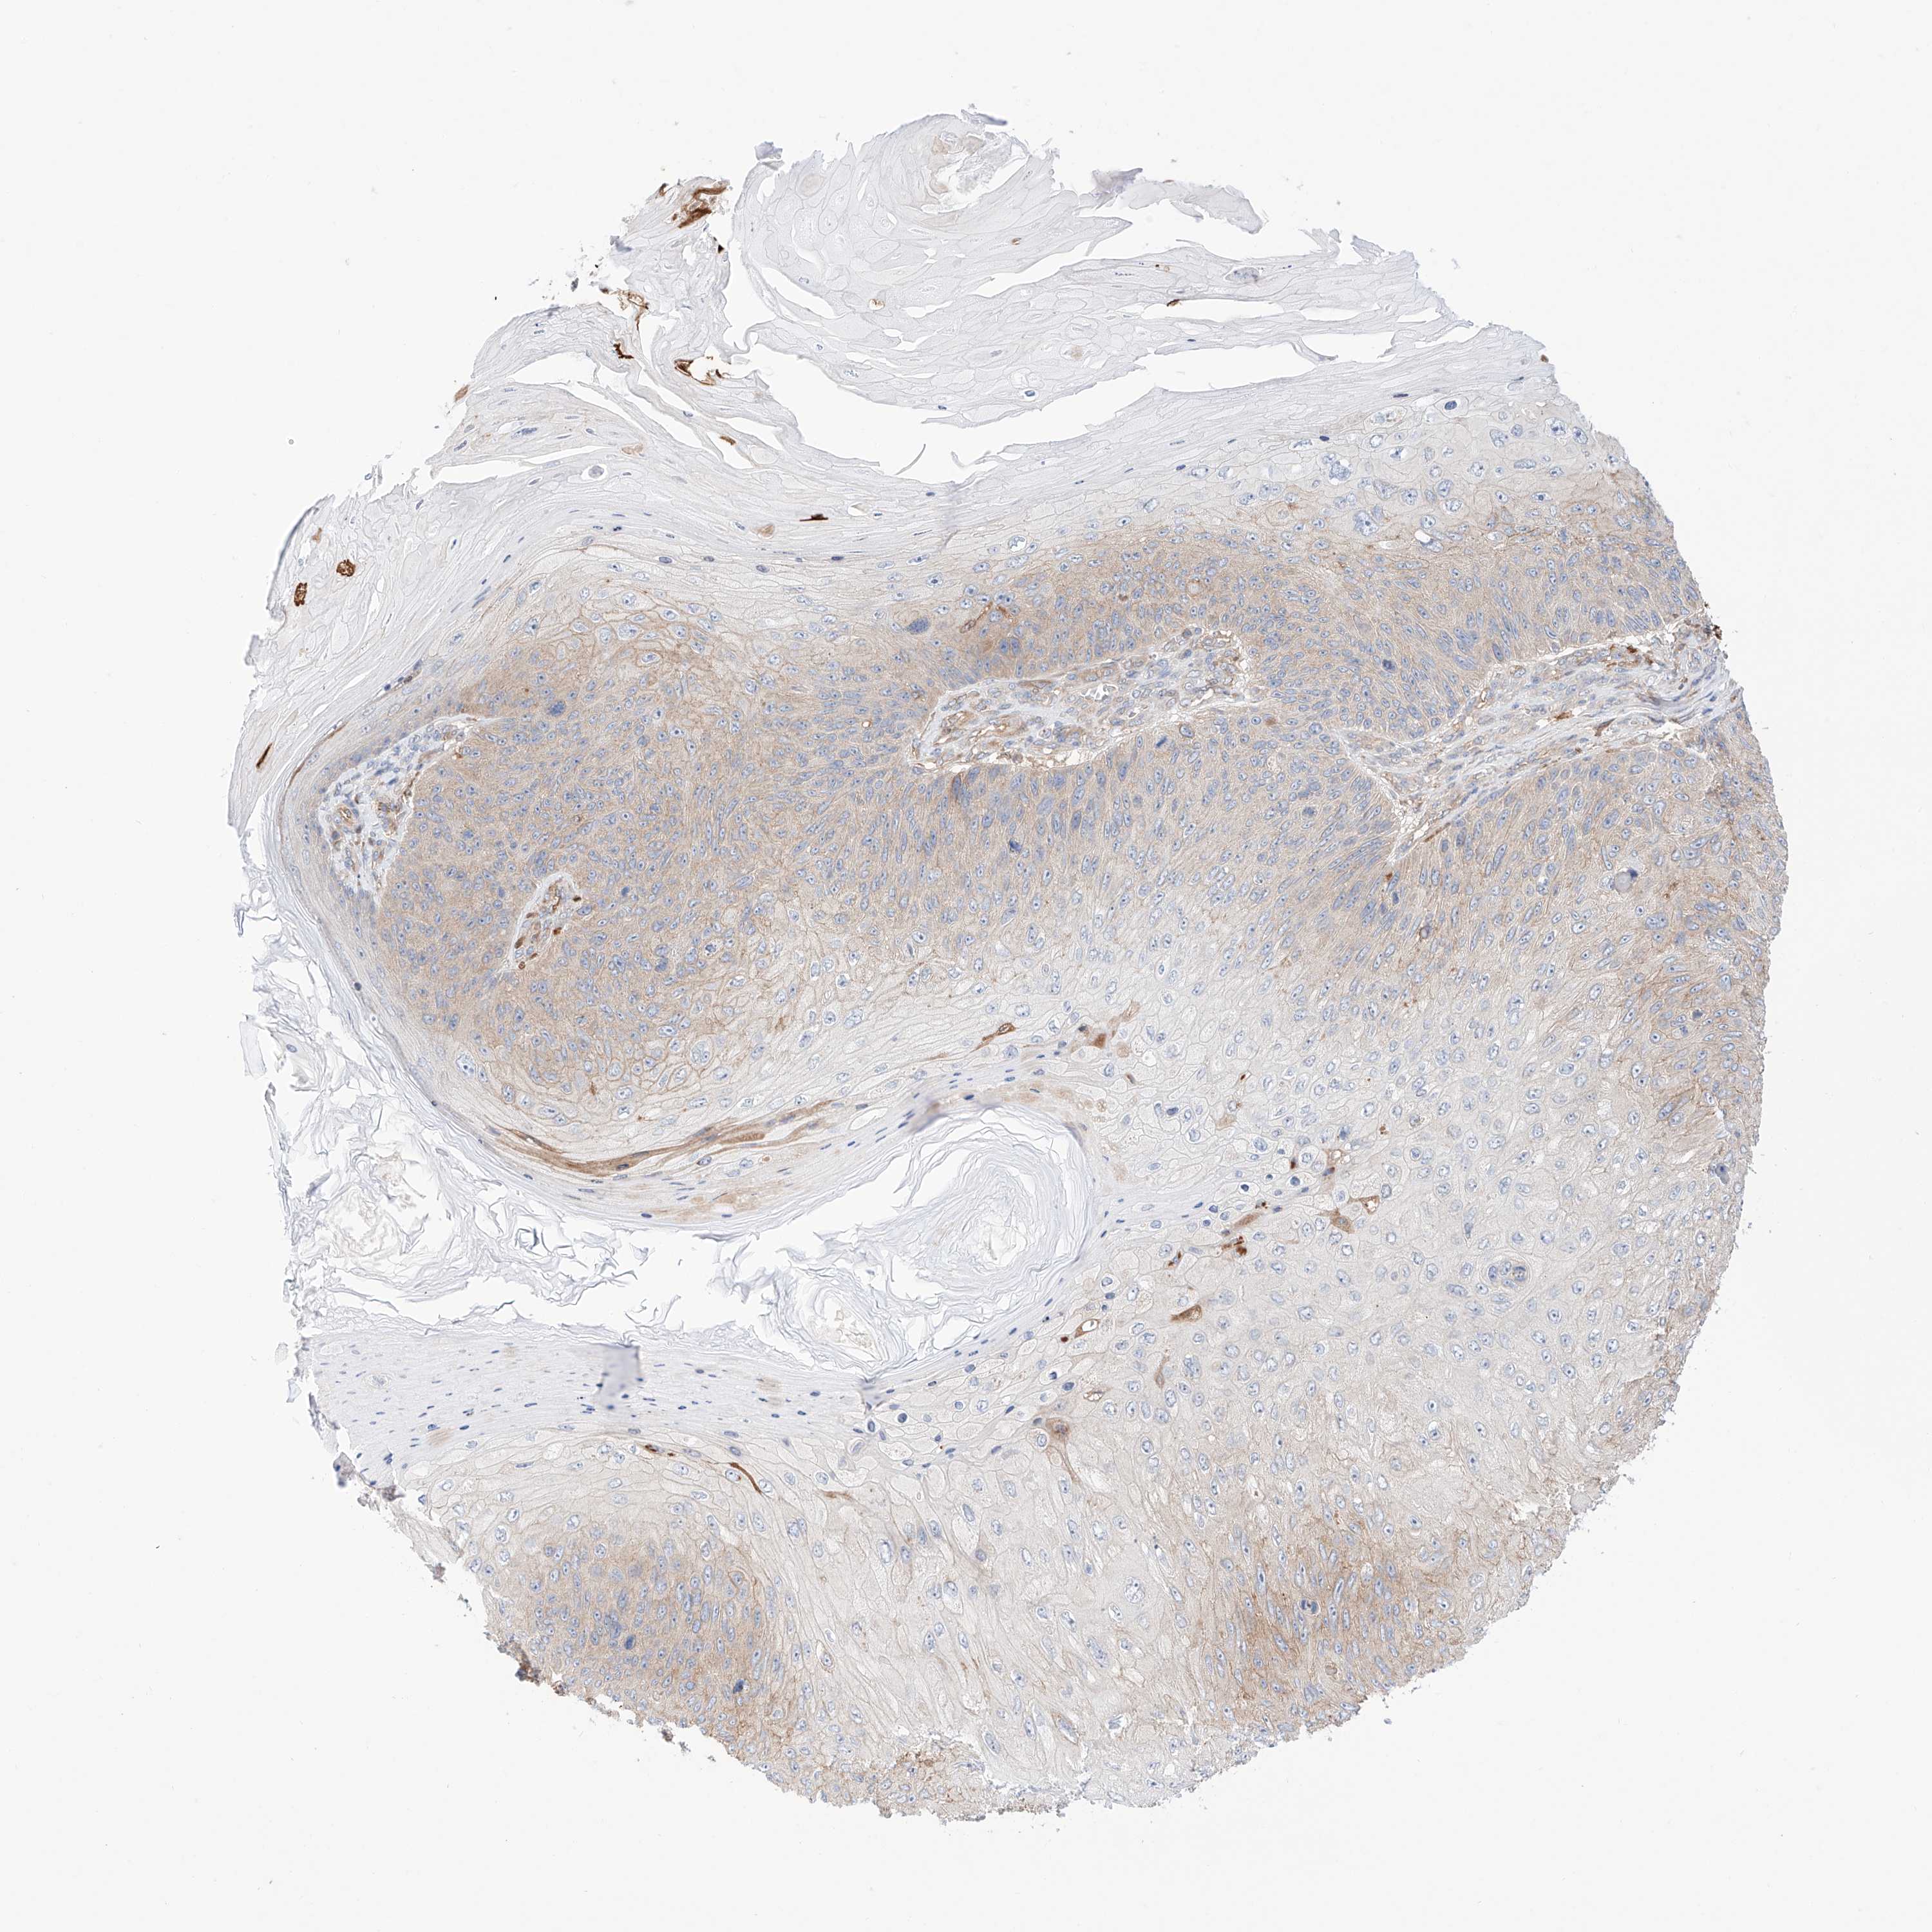

Basal cell and squamous cell cancer

SKIN CANCER - Protein expressioni

A mouse-over function shows sample information and annotation data. Click on an image to view it in a full screen mode. Samples can be filtered based on level of antibody staining by selecting one or several of the following categories: high, medium, low and not detected. The assay and annotation is described here.

Each image is clickable and will lead to virtual microscopy that enables deeper exploration of all samples and also displays staining intensity scores, fraction scores and subcellular localization as well as patient and tissue information for each sample.

Antibody HPA030646

Staining

Low

Strong

>75%

Location

Cytoplasmic/membranous

Squamous cell carcinoma, metastatic, NOS

Squamous cell carcinoma, NOS